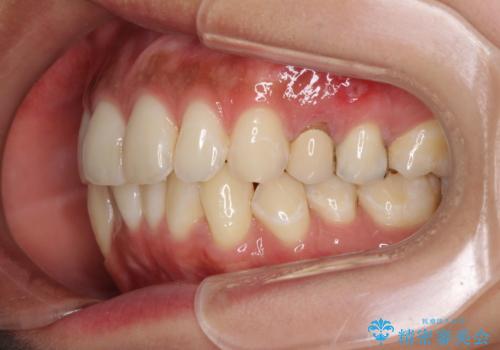

下顎の八重歯が上顎歯列に収まる過程で咬みにくさがありましたが、最終的には、咬み合わせも安定し、きれいに歯列を整えることができました。

矯正治療後には根管治療を行った歯の補綴治療を行うこととしました。